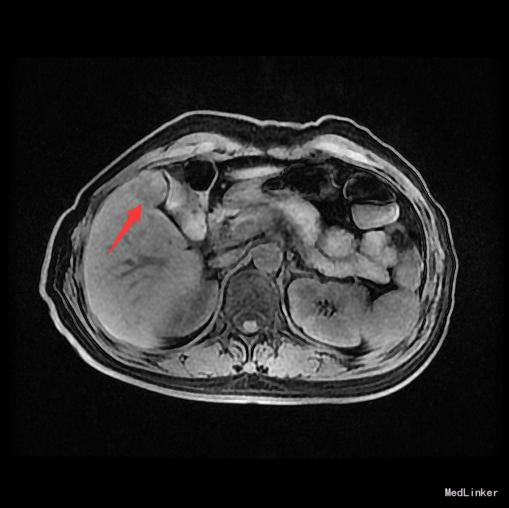

辅查:AFP 3.43ng/ml, CEA 1.47ng/ml。MR:肝S5段占位性病变(26*25mm),考虑肝癌可能性大,建议活检。

随访:术后病理示:(右肝肿物)送检肝组织部分呈结节状增生,结节间见粗细不等的纤维间隔,其内见血管增生,少量淋巴细胞及浆细胞浸润,符合肝局灶性结节状增生(FNH)。 讨论:肝局灶性结节增生(FNH)是肝内第二常见良性肿瘤,一般无临床症状,影像学表现,MRI上T1WI和T2WI与周围肝实质信号相近,增强扫描动脉期明显强化,若存在中央瘢痕,则中央瘢痕不强化,门脉期及静脉期强化程度减退,中央瘢痕则呈延迟强化。FNH需与肝癌和肝腺瘤鉴别,本例即误诊为肝癌,若存在中央瘢痕,则诊断较容易。